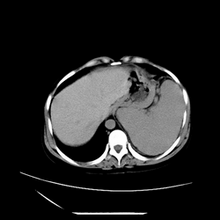

女性,41岁,发现左腹部包块3年,现行ct检查,检查前做过静脉肾盂造影。

左侧低密度区是脂肪密度,中间可见条索状软组织样密度影,现主要想知道左肾前下缘圆形软组织样密度影,内见低密度水样密度影,这是什么?

脾脏增大,左肾后方脂肪增多,脊柱前方脂肪增多,左肾窦脂肪增多,左肾变形,双肾积水以左侧为著,左肾内侧及上方见环形软组织肿物影,内部低密度区,考虑1盆腹腔/腹膜后及左肾窦脂肪增多症2左肾内侧病灶可能为左肾上腺病灶,可能为脂肪增多的原凶

1)考虑左肾替代性脂肪瘤病;不排除左肾错构瘤。2)双肾积水。

肾窦脂肪瘤病及肾替代性脂肪瘤病被认为是脂肪增殖程度不同的一种疾病。正常情况下肾窦内有少量脂肪组织充填,在某种情况下肾实质会发生萎缩,而以肾窦、肾门为中心脂肪或(和)纤维组织可出现增殖,当增殖局限在肾窦、肾门区时称为肾窦脂肪瘤,若同时部分或全部取代了萎缩破坏的肾实质时称为肾替代性脂肪瘤病。

发病机理有2种学说,大部分人认为是由于某些具有破坏性的肾脏疾病,如肾结石并感染、肾结核等造成肾破坏、萎缩,继发了大量的脂肪组织增殖;另一部分则认为肾脏慢性炎症可刺激脂肪组织的增殖,肾萎缩是继发的。

ct典型表现为以肾窦肾门为中心大量弥漫性脂肪积聚,鹿角状结石及萎缩的肾实质。合并肾周感染时,肾轮廓不清,周围有粘连性改变。

诊断主要需与含脂肪的肾肿瘤加以区别,如血管平滑肌脂肪瘤、脂肪肉瘤、脂肪瘤